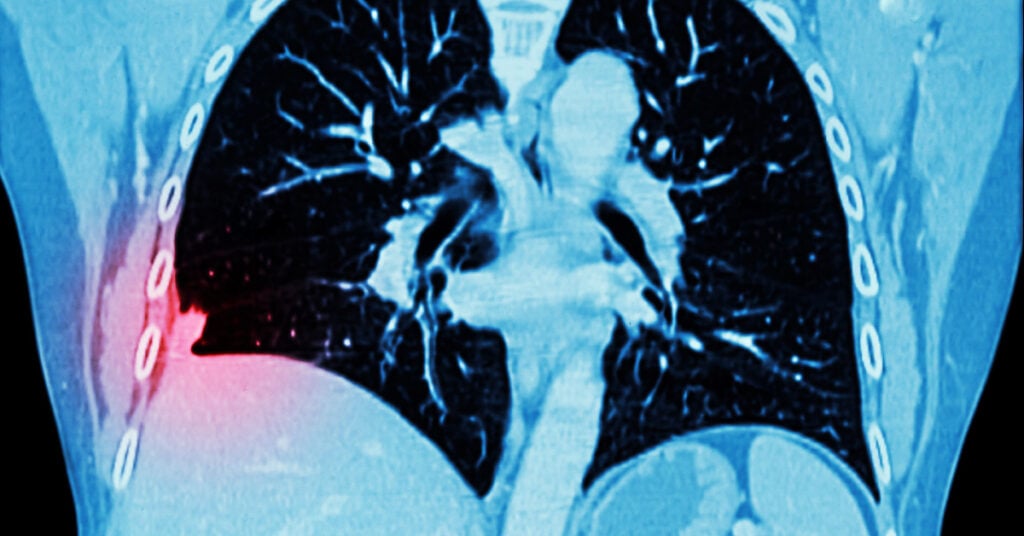

Chụp CT phổi (Computed Tomography – CT scan của phổi) là một phương pháp y khoa không gây tổn thương, không gây đau đớn. Phương pháp này thực hiện thông qua việc sử dụng tia X để tạo ra các hình ảnh chi tiết của phổi và cấu trúc xung quanh cơ quan này. Quá trình này giúp bác sĩ xác định và đánh giá các vấn đề về sức khỏe của phổi như: Bệnh phổi, nhiễm trùng phổi, khối u hoặc các tổn thương khác,…

- Hình ảnh chi tiết: CT phổi tạo ra các hình ảnh chi tiết hơn so với các phương pháp hình ảnh khác. Từ đó, có thể giúp cho việc chẩn đoán và quan sát rõ hơn các vùng bị tổn thương hoặc bất thường của bác sĩ cũng chính xác hơn.

Chụp CT phổi có khả năng phát hiện ra các vấn đề về phổi, bao gồm bệnh ung thư phổi. Tuy nhiên, khả năng phát hiện phụ thuộc vào kích thước và loại bệnh ung thư, vị trí và các yếu tố khác.